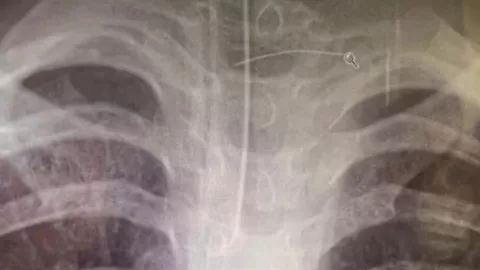

Tras una serie de estudios, los médicos encontraron abscesos en el cerebro que eran producidos por un alambre, indicando que estos se dieron luego de que el pedazo de metal entrara a través de algún alimento.

El objeto le atravesó el esófago y entró hasta su arteria carótida, en el cuello. Ante la gravedad de la situación tuvo que ser trasladada en helicóptero a otro hospital para que la atendieran cirujanos especialistas.